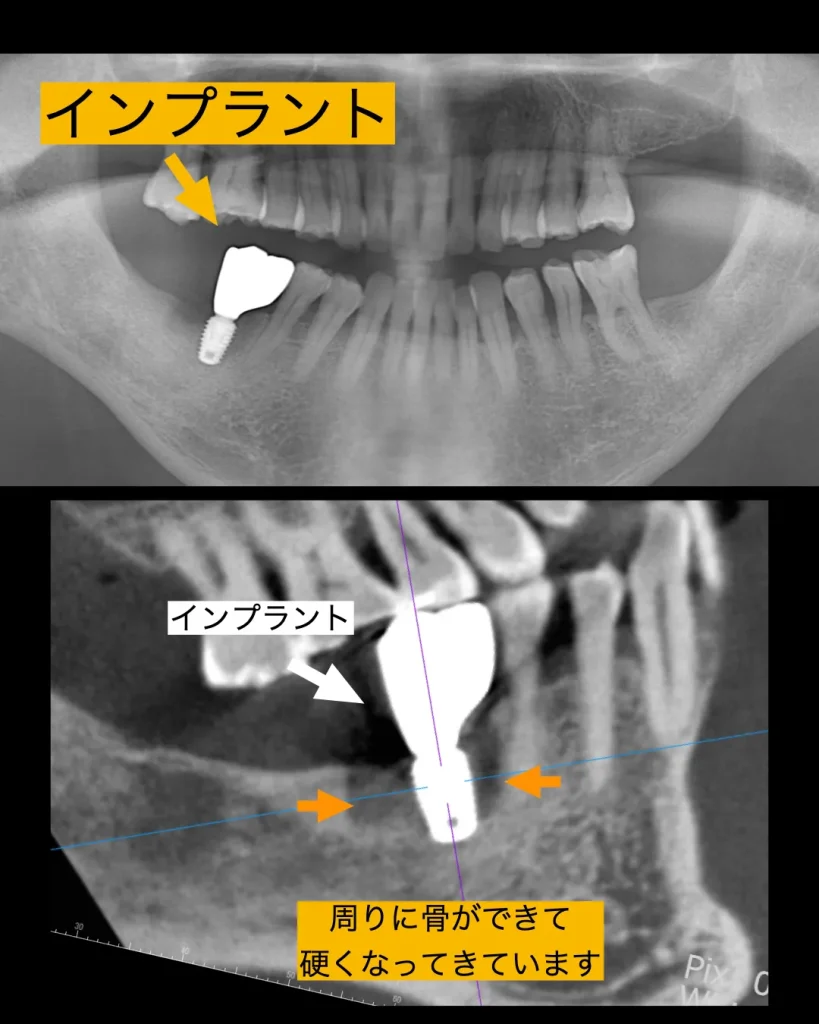

歯肉は2ヶ月ほどで治癒し、3ヶ月ほどで骨硬化像もでてきました。ISQと呼ばれるインプラントが骨と生着し硬くなっている値を測定する機械で測ると十分な値を得ることができました。仮歯の型採りを口腔内スキャナーで行い、セットし、頬を噛まないか・舌を噛まないか・しっかりとお食事ができるかをチェックし、問題ないことを確認しました。

セットまで3ヶ月ちょっとで終了することができ、患者様は大喜びされました。これは抜歯即時インプラントができたことによるものです。